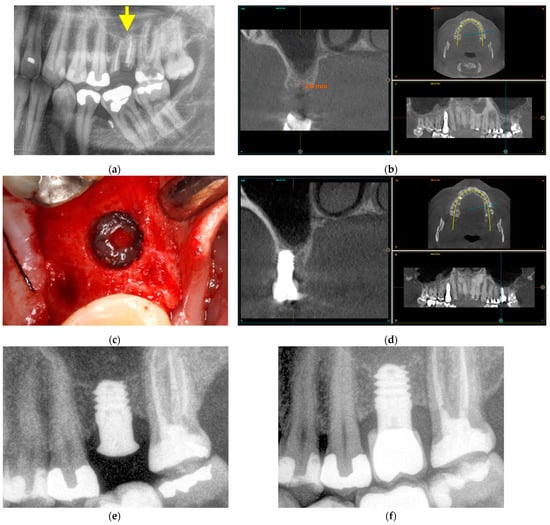

3.3.1. Vertical Bone Atrophy in the Mandible

The first case is shown in Figure 7 and corresponds to vertical bone atrophy in the lower jaw with a residual bone height of 4 mm above the alveolar nerve (Figure 7a). The placement of the implant was performed just above the nerve leaving a portion of the implant neck exposed buccolingually (Figure 7b). The exposed area of the implant was covered using the patient’s own bone mixed with PRGF-Endoret® (Figure 7c). The slow-drilling procedure for the implant-site preparation (125 rpm without irrigation) allows the recovery of bone from the patient that, once mixed with PRGF-Endoret®, forms a flexible membrane with embedded bone particles. This membrane can be shaped to fill biological gaps or to overcorrect situations like the one described above [17]. Figure 7d,e shows how already, 4 months after the placement of the implant, the regenerated bone is covering the implant completely. The stability of this bone is maintained 5 years after the surgery (Figure 7e).

Figure 7.

Vertical bone atrophy in the jaw with a residual bone height of 4 mm (a). Insertion of the dental implant leaving a part of the implant exposed, which was covered using bone recovered from the site preparation mixed with PRGF-Endoret® (b,c). At 4 months (d,e), vertical bone regeneration can be observed covering the implant (yellow arrow). Stability of the regenerated bone at 5 years follow-up (f).

3.3.2. Maxillary Sinus Floor Augmentation

The second case corresponds to an upper jaw with severe vertical bone resorption (Figure 8). The tooth roots were removed due to infection (Figure 8a), and the site was filled with PRGF-Endoret®. After three months, the available vertical height was 3 mm (Figure 8b). In the surgery plan, the bone density of the site was measured, and an extra short unicCa® implant 5.5 mm in length was planned. The surgery was carried out with a frontal attack drill (Figure 8c) up to the sinus membrane. The membrane is lifted gently with autologous bone from the osteotomy mixed with PRGF-Endoret® and retained in position after the positioning of the implant (Figure 8d,e). Soon after the surgery, the peri-implant bone height was 4.5 mm. Five years after the surgery, the bone height was stable around the implant and in its apical part (Figure 8f). The new vertical bone height was 7.5 mm.

Figure 8.

Maxillary sinus floor augmentation. Prior extraction of the infected tooth roots, marked with a yellow arrow (a). Three months after extraction, the residual bone height is 3 mm (b). The sinus membrane was gently pushed upwards with autologous bone recovered from the site preparation mixed with PRGF-Endoret® (c). A 5.5 mm short implant is placed at the implant site to support the sinus floor elevation apically (d). Three months after implant placement, the bone height around the implant was 4.5 mm (e). Five years after the placement of a short implant, the measured bone height at the implant site was 7.5 mm (f).